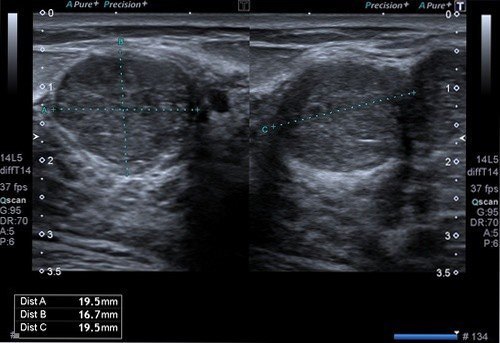

Meme ultrasonu ile yukarda tarif ettiğimiz takipler dışında, meme kitlelerinin, meme kistlerinin, meme enfeksiyonları ve abselerinin, meme süt kanallarındaki genişleme ve içlerindeki olası kitlelerin, meme içerisindeki lenf bezlerinin, damarsal ya da cilt altı yağ doku kaynaklı kitlelerin tanısı konulabilir.

Memede saptanan kitlelerin ultrasonu özelliklerinin değerlendirilmesi ile iyi huylu, kötü huylu ya da şüpheli olduğu söylenebilir. İyi huylu kitlelerin normal meme dokusuna göre kötü huylu kitlelerle dönüşmesinin riski daha yüksek olduğu için 3 ya da 6 ay aralıklarla meme ultrasonu ile takip edilmelidir. Şüpheli kitlelerin kısa aralıkla takibi, mamografi ve meme MRG ile değerlendirilmesi gerekebilir. Meme ultrasonunda büyük olasılıkla kötü huylu olduğu düşünülen kitleler için ise meme ultrasonu eşliğinde biyopsi yapılması gerekecektir.